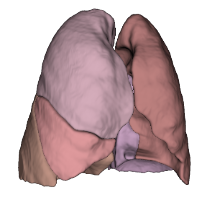

Built on advanced capabilities in lung segmentation and quantification, our AI technology interprets thoracic CT data with anatomical precision - capturing airway trees, parenchymal patterns, and vascular structures, even in severely diseased lungs.

- Segmentation of anatomical structures up to sub-segmental level